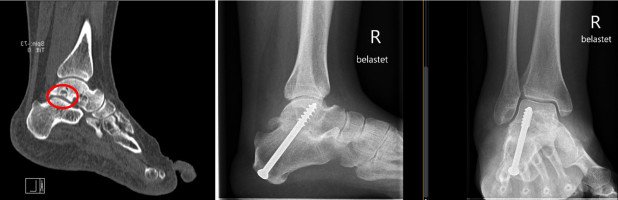

Eine 33-jährige Verkäuferin stellt sich im Rahmen unserer Sprechstunde mit belastungsabhängigen Rückfussschmerzen vor. Diese bestünden seit sie sich bei einem Treppensturz 8 Monate zuvor eine kleine Fraktur des Fersenbeins zugezogen habe. In der mitgebrachten MRI-Untersuchung sieht man degenerative Veränderungen des unteren Sprunggelenkes, welches sich zwischen Sprungbein und genanntem Fersenbein befindet. Die Fersenbeinfraktur begünstigte hier mit ihren Ausläufern ins Gelenk die degenerativen Veränderungen.

Mittels der dann durchgeführten Infiltration konnte der Schmerz zumindest vorübergehend gelindert werden, kam aber nach einiger Zeit zurück. Da so aber zusätzlich nochmals das untere Sprunggelenk als Schmerzursache identifiziert werden konnte, entschlossen wir uns bei entsprechendem Leidensdruck der Patientin gemeinsam mit ihr für das operative Vorgehen und es erfolgte die Versteifung des unteren Sprunggelenkes.

Hiernach wurden der Fuss und der Unterschenkel mit einem speziellen Stiefel als Gips-Ersatz für 6 Wochen ruhiggestellt und das Bein mittels Unterarmgehstöcken mit maximal 15 kg belastet. Während dieser Zeit erfolgte die Thromboseprophylaxe mit einer Tablette, da ansonsten bei einer derartigen Ruhigstellung und Entlastung die Gefahr einer Thrombose erhöht wäre. 6 Wochen nach der Operation zeigte sich in der Röntgenaufnahme ein regelrechter Verlauf, so dass langsam zur Vollbelastung übergegangen werden konnte: der Spezialstiefel wurde noch für 2 Wochen getragen, die Stöcke immer mehr weggelassen. 2 Monate nach der Operation konnte die Patientin in normalem Konfektionsschuhwerk bereits laufen, wobei hier zunächst Schuhe mit einer stabilen Sohle und einer Abrollrampe im Vorfussbereich verwendet werden sollten. 3 Monate nach der Operation war die Patientin nahezu beschwerdefrei, die Versteifung in der Röntgenuntersuchung konsolidiert. 6 Monate nach der Operation präsentiert sich eine beschwerdefreie Patientin.